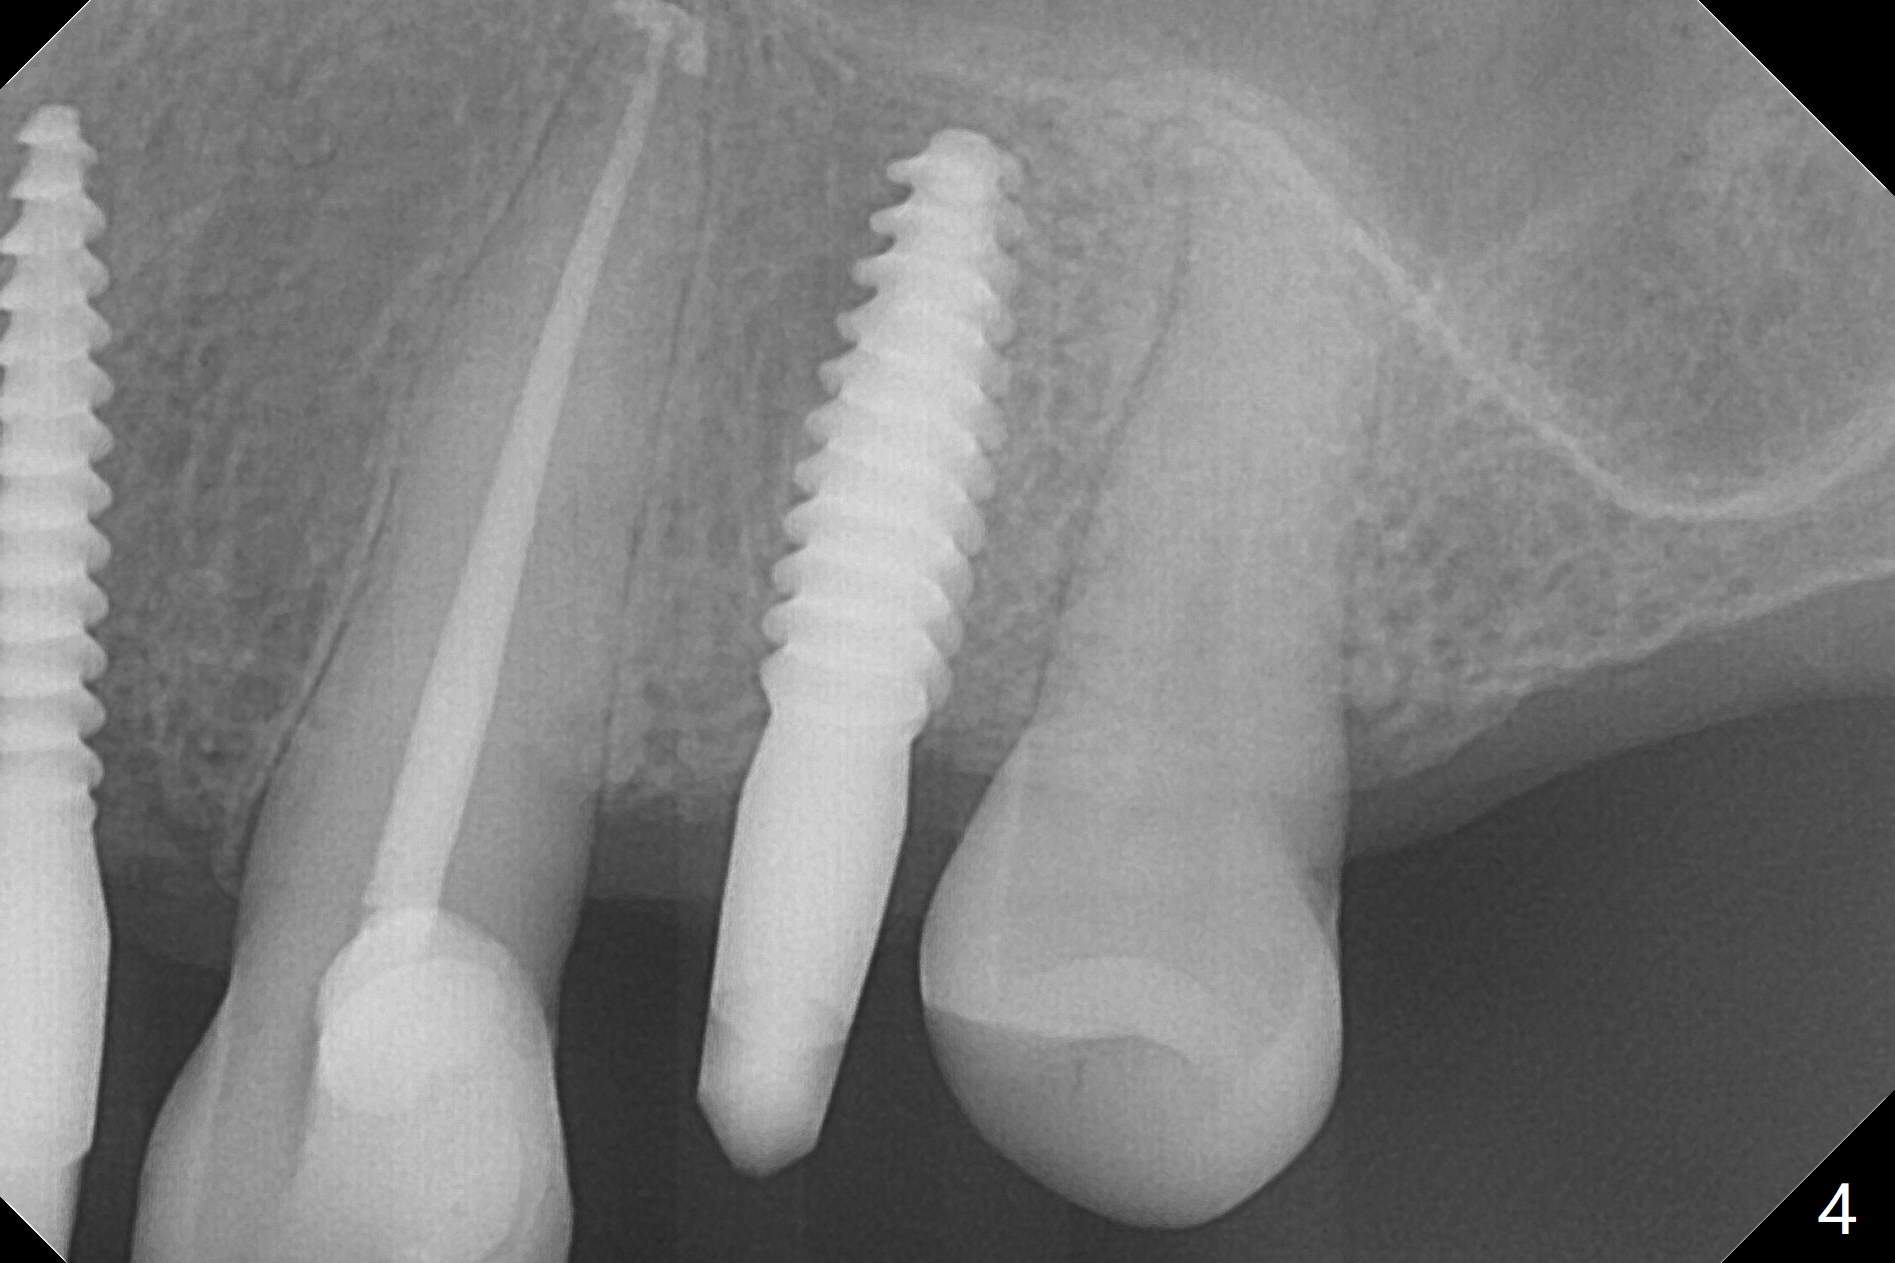

After removal of #10 sleeve and 3 spot adjustment, the guide is seated without satisfaction. When the guide is removed after pointed drill, the osteotomy seems distal (Fig.1). Incision is made with flap elevation for free hand osteotomy. A 1/1.6 mm bone expander is inserted after 1.2 mm drill, the trajectory appears to be right (Fig.2). As the osteotomy increases in diameter, the buccal plate feels to be vibratory. A 3.5x11.5 mm 1-piece implant placed initially is apparently away the sinus floor (Fig.3). Further placement (subcrestal, Fig.4) seems to be associated with more buccal plate perforation (Fig.6 *), which is repaired by bone graft. Since the implant at #10 appears to be doing okay 1.5 months postop (Fig.5), the implant at #12 is not removed immediately. A tunnel incision will be made for bone graft in the most apical concave areas (Fig.7). The osteotomy should have been made more palatal to reduce the chance of the buccal perforation. CBCT should have been taken while the 1/1.6 bone expander was in place.